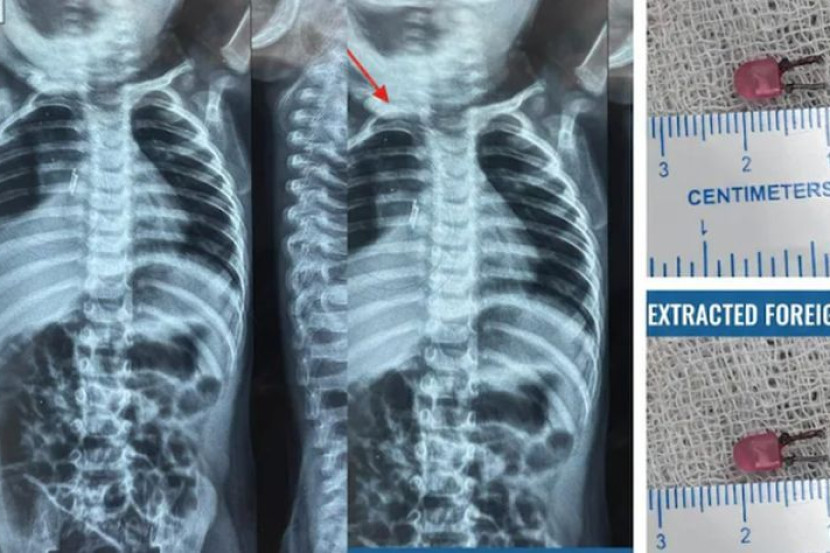

医疗团队随即紧急安排支气管镜检查(Bronchoscopy),经过一番精细的手术操作,医生成功从男童狭窄的气管深处,夹出了一枚长约1公分的发光二极管(LED)灯泡。真相大白后,在场医护人员与家属皆感到震惊不已。

希伦索尼医生指出,这枚小小的电子元件正是导致男童长期咳嗽和发烧的罪魁祸首。所幸在现代医疗仪器的辅助下,异物被顺利取出,男童在术后也迅速恢复健康,逃过一劫。